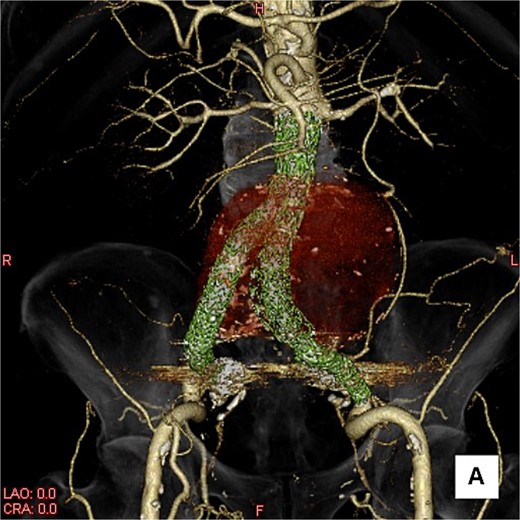

Contrast-enhanced CT revealed an AAA measuring 118 × 107 mm and left retroperitoneal hematoma. One pair of lumbar arteries was enhanced only in the delayed phase (red arrows). Intraoperatively, pulsatile bleeding was observed from the left one of this pair.

This time, he was brought to the emergency department with a chief complaint of abdominal pain. His medical history includes Stage 4–5 chronic kidney disease (CKD), with an estimated glomerular filtration rate (eGFR) of approximately 15 mL/min/1.73 m2, secondary to nephrosclerosis and diabetic nephropathy, as well as persistent atrial fibrillation, which was treated with warfarin. Upon admission, laboratory results revealed a hemoglobin level of 6.2 g/dl and a prothrombin time—international normalized ratio (PT-INR) of 6.05. Contrast-enhanced CT demonstrated an AAA measuring 118 × 107 mm, enlarged from 98 × 94 mm 2 months prior, and left retroperitoneal hematoma. IMA and one pair of lumbar arteries were enhanced only in the delayed phase, but blood flow into the aneurysm was not clearly observed (Fig. 1). Given that the landing zones and overlaps of the stent grafts were satisfactory (Fig. 2) and that no type I or type III endoleaks were identified, a ruptured AAA due to TIIEL from the lumbar artery or IMA was highly suspected. We administered 3000 IU/kg of lyophilized human prothrombin complex concentrate in response to the significant prolongation of PT-INR and proceeded with open surgery for ligation of the feeding artery and aneurysmorrhaphy. Intraoperatively, no pulsation was found on the aneurysm. Incision of the aneurysm revealed a large amount of thrombus, which was removed, and then pulsatile bleeding was identified from a lumbar artery (Fig. 3), the ostium of which was sutured from within the aneurysm. This was consistent with the left lumbar artery of the pair enhanced on the preoperative CT and was suspected to be responsible for the rupture. Oozing was also noted from several other lumbar arteries, which were similarly sutured closed. No leak was observed from the proximal or distal ends, nor from the junctions of the stent grafts, and no damage to the stent grafts was observed (Fig. 4). Following this, aneurysmorrhaphy was performed, and the abdomen was closed. The postoperative course was uneventful. A plain CT on postoperative day (POD) 14 showed a reduction in the aneurysm size with no apparent leaks (Fig. 5). The patient was discharged home on POD 24. Although the preoperative eGFR was 8.8 ml/min/1.73 m2, no postoperative deterioration was observed. It gradually improved back to baseline, and dialysis was not required during the follow-up period.